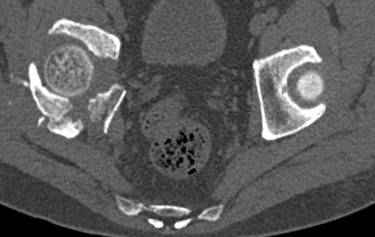

Интересно было бы посмотреть рентгенограммы до операции. У меня впечатление, что я не все вижу, что тут есть... Уважаемые Господа "тазисты" и "тазологи", к какому типу переломов вертлужной впадины по Летурнелю вы бы отнесли это случай?

Из переломов проходящих через крыло и/или заднюю стенку ни простой перелом "передней колонны" (явно имеется пером задней стенки, и не видно перелома седалищной или лонной), ни простой "поперечный", ни ассоциированный "Т-образный" (т.к есть перелом крыла и не видно перелома седалишной), ни ассоциированный "задняя колонна+задняя стенка", на ассоциированный "поперечный+задняя стенка", ни ассоциированный "передняя колонна+задняя гемисфера" (не видно перелома седалищной), ни ассоциированный "обе колонны" (не видно перелома лонной седалищной) не подходят под эту классификацию....

к таковым себя не причисляю, но...обычное дело для нашей страны - выкладывать 3D и не показывать стандартные проекции Judet. Дигност представляет те ракурсы, которые по-его мнению наиболее информативны, более того комп сам достраивает какие-то мелкие повреждения по 3D по своему усмотрению. По данной реконструкции можно предполагать высокий двухколонный перелом с оскольчатыми передней и задней колоннами, оскольчатую высокую переднюю колонну с задним полупоперечником или одно из перечисленных с вовлечение КПС. У меня впечатление за второй вариант, но нужно обследовать нормально - проекции, сканы.

высылаю дополнительно сканы.